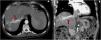

Un hombre de 49 años presentó sangrado de várices esofágicas y, además, se le diagnosticó cirrosis relacionada con enfermedad de hígado graso asociado a disfunción metabólica. El paciente fue referido a continuación a nuestro centro para investigar nódulos hepáticos detectados por medio de ultrasonido. El paciente estaba asintomático, con una clasificación de Child-Pugh A5 y puntuación de MELD de 12. Una tomografía computarizada (TC) de contraste del abdomen mostró CHC multinodular/infiltrante, con un trombo tumoral en la vena hepática derecha que se extendía a la vena cava inferior (fig. 1). Además, se identificaron émbolos en el lóbulo inferior del pulmón izquierdo en la TC de tórax (fig. 2). La alfafetoproteína sérica fue de 509 ng/ml, el gammagrama óseo no presentó alteraciones y el ecocardiograma transtorácico no mostró extensión al corazón.

Tomografía computarizada en la fase arterial: carcinoma hepatocelular infiltrante y multinodular con lesión hipodensa entre los segmentos V/VIII con medidas de 60mm en su diámetro más grande (necrosis). Se observa un trombo en la imagen de contraste dentro de la vena hepática derecha (flechas rojas) que se extiende hacia la vena cava inferior. A) Plano transversal. B) Plano coronal.